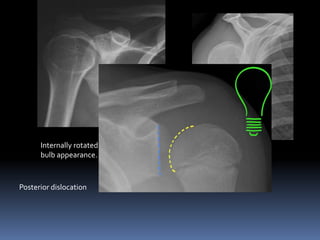

History of Trauma

CASE 1O

AP shoulder

Y view or scapula lateral

Internally rotated humerus giving light

bulb appearance. Y view showing

Posterior dislocation

posterior

dislocation.